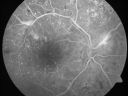

Capillary Non-Perfusion - Severe Non-Proliferative (Background) Diabetic Retinopathy - Type I - 20 Year Old Man Diabetic 16 years601 views20 year old diabetic with poor vision for the past three or four years. He has been diabetic for sixteen years and hemoglobin A1C of 10.0. 20/25 OD, 20/30 OS. Sep 20, 2011

|